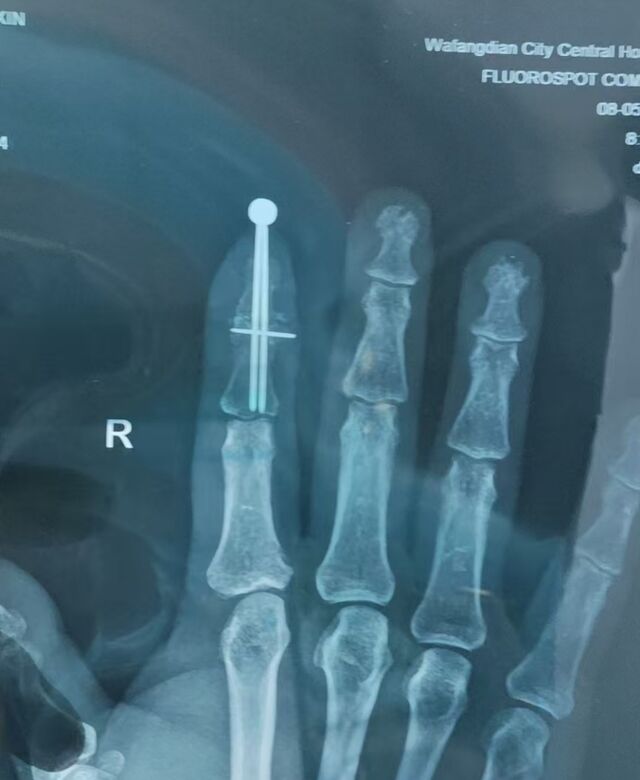

门诊经常遇到特殊病例

在韩国做的手术

未住院,手术费用折合人民币大概7万

这个克氏针尾帽,让我眼前一亮

还是内六角螺丝固定的

从X线片看,应该是做的DIP关节融合术

里边居然是3枚克氏针

本帖最后由 zhangwenlong 于 2025-6-2 08:47 编辑

从外观像看,以为这个尾帽仅是做完美外观,防止克氏针针尾划伤身体,或者防止别勾带出来的目的

从X线片看,这个尾帽可能有更多的目的和意义

比如:不平行置钉,针尾链接,起到提高弹性把持力作用;

再或者,有没有可能是绞锁髓内钉的用法呢

看3枚克氏针交汇处,特像绞锁髓内钉